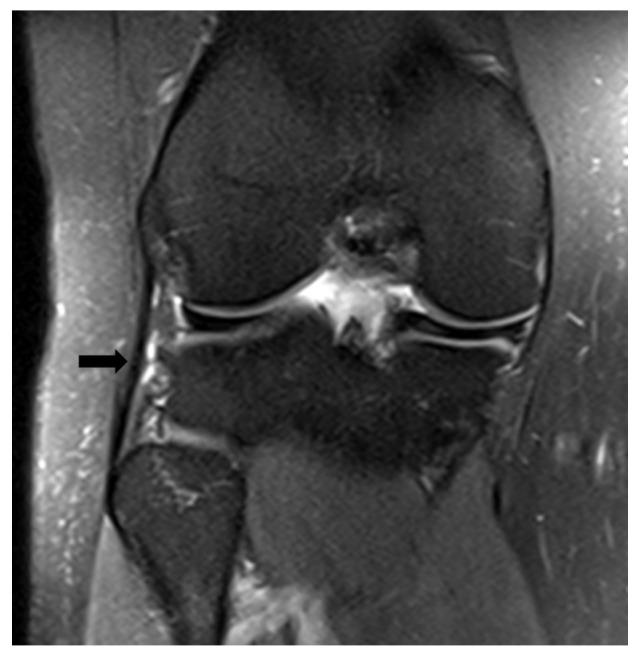

The aim of this study was to evaluate the presence of residual instability in the knee after ACL reconstruction through the analysis of MRI findings. This study included patients who underwent isolated ACL reconstruction between December 2019 and December 2021, and had preoperative and postoperative MRI, clinical scores, and postoperative isokinetic measurements. The anterior tibial translation (ATT) distance, coronal lateral collateral ligament (LCL) sign, and femorotibial rotation (FTR) angle were compared preoperatively and postoperatively. The correlation between the changes in preoperative-postoperative measurements and postoperative measurements with clinical scores and isokinetic measurements was examined. The clinical outcomes were compared based on the presence of a postoperative coronal LCL sign. Inclusion criteria were set as follows: the time between the ACL rupture and surgery being 6 months, availability of preoperative and postoperative clinical scores, and objective determination of muscle strength using isokinetic dynamometer device measurements. Patients with a history of previous knee surgery, additional ligament injuries other than the ACL, evidence of osteoarthritis on direct radiographs, cartilage injuries lower limb deformities, and contralateral knee injuries were excluded from this study. This study included 32 patients. After ACL reconstruction, there were no significant changes in the ATT distance (preoperatively: 6.5 ± 3.9 mm, postoperatively: 5.7 ± 3.2 mm) and FTR angle (preoperatively: 5.4° ± 2.9, postoperatively: 5.2° ± 3.5) compared to the preoperative measurements ( > 0.05). The clinical measurements were compared based on the presence of a postoperative coronal LCL sign (observed in 17 patients, not observed in 15 patients), and no significant differences were found for all parameters ( > 0.05). There were no observed correlations between postoperative FTR angle, postoperative ATT distance, FTR angle change, and ATT distance change values with postoperative clinical scores ( > 0.05). Significant correlations were observed between the high strength ratios generated at an angular velocity of 60° and a parameters FTR angle and ATT distance (-values: 0.028, 0.019, and r-values: -0.389, -0.413, respectively). Despite undergoing ACL reconstruction, no significant changes were observed in the indirect MRI findings (ATT distance, coronal LCL sign, and FTR angle). These results suggest that postoperative residual tibiofemoral rotation and tibial anterior translation may persist; however, they do not seem to have a direct impact on clinical scores. Furthermore, the increase in tibial translation and rotation could potentially negatively affect the flexion torque compared to the extension torque in movements requiring high torque at low angular velocities.

本研究旨在通过 MRI 检查结果分析评估 ACL 重建后膝关节的残余不稳定情况。本研究纳入了 2019 年 12 月至 2021 年 12 月期间接受单纯 ACL 重建的患者,且患者术前、术后均行 MRI、临床评分和术后等速测量。比较术前和术后胫骨前移(ATT)距离、冠状外侧副韧带(LCL)征和股骨胫骨旋转(FTR)角度。检查术前-术后测量值与术后临床评分和等速测量值之间的变化相关性。根据术后冠状 LCL 征的存在比较临床结果。纳入标准如下:ACL 破裂至手术的时间为 6 个月,术前、术后临床评分可用,使用等速测力计设备测量客观确定肌肉力量。排除既往膝关节手术史、除 ACL 以外的其他韧带损伤、直接 X 线片上骨关节炎证据、软骨损伤、下肢畸形和对侧膝关节损伤的患者。本研究共纳入 32 例患者。ACL 重建后,ATT 距离(术前:6.5 ± 3.9mm,术后:5.7 ± 3.2mm)和 FTR 角度(术前:5.4°±2.9°,术后:5.2°±3.5°)与术前测量值相比无显著变化(>0.05)。根据术后冠状 LCL 征的存在比较临床测量值(观察到 17 例,未观察到 15 例),所有参数均无显著差异(>0.05)。术后 FTR 角度、术后 ATT 距离、FTR 角度变化和 ATT 距离变化值与术后临床评分之间无观察到相关性(>0.05)。在角速度为 60°时产生的高力量比与 FTR 角度和 ATT 距离参数呈显著相关性(-值:0.028、0.019,r 值:-0.389、-0.413)。尽管进行了 ACL 重建,但间接 MRI 检查结果(ATT 距离、冠状 LCL 征和 FTR 角度)未见明显变化。这些结果表明,术后胫骨股骨旋转和胫骨前移可能持续存在,但它们似乎对临床评分没有直接影响。此外,与伸展扭矩相比,在需要低角速度高扭矩的运动中,胫骨平移和旋转的增加可能对屈曲扭矩产生负面影响。